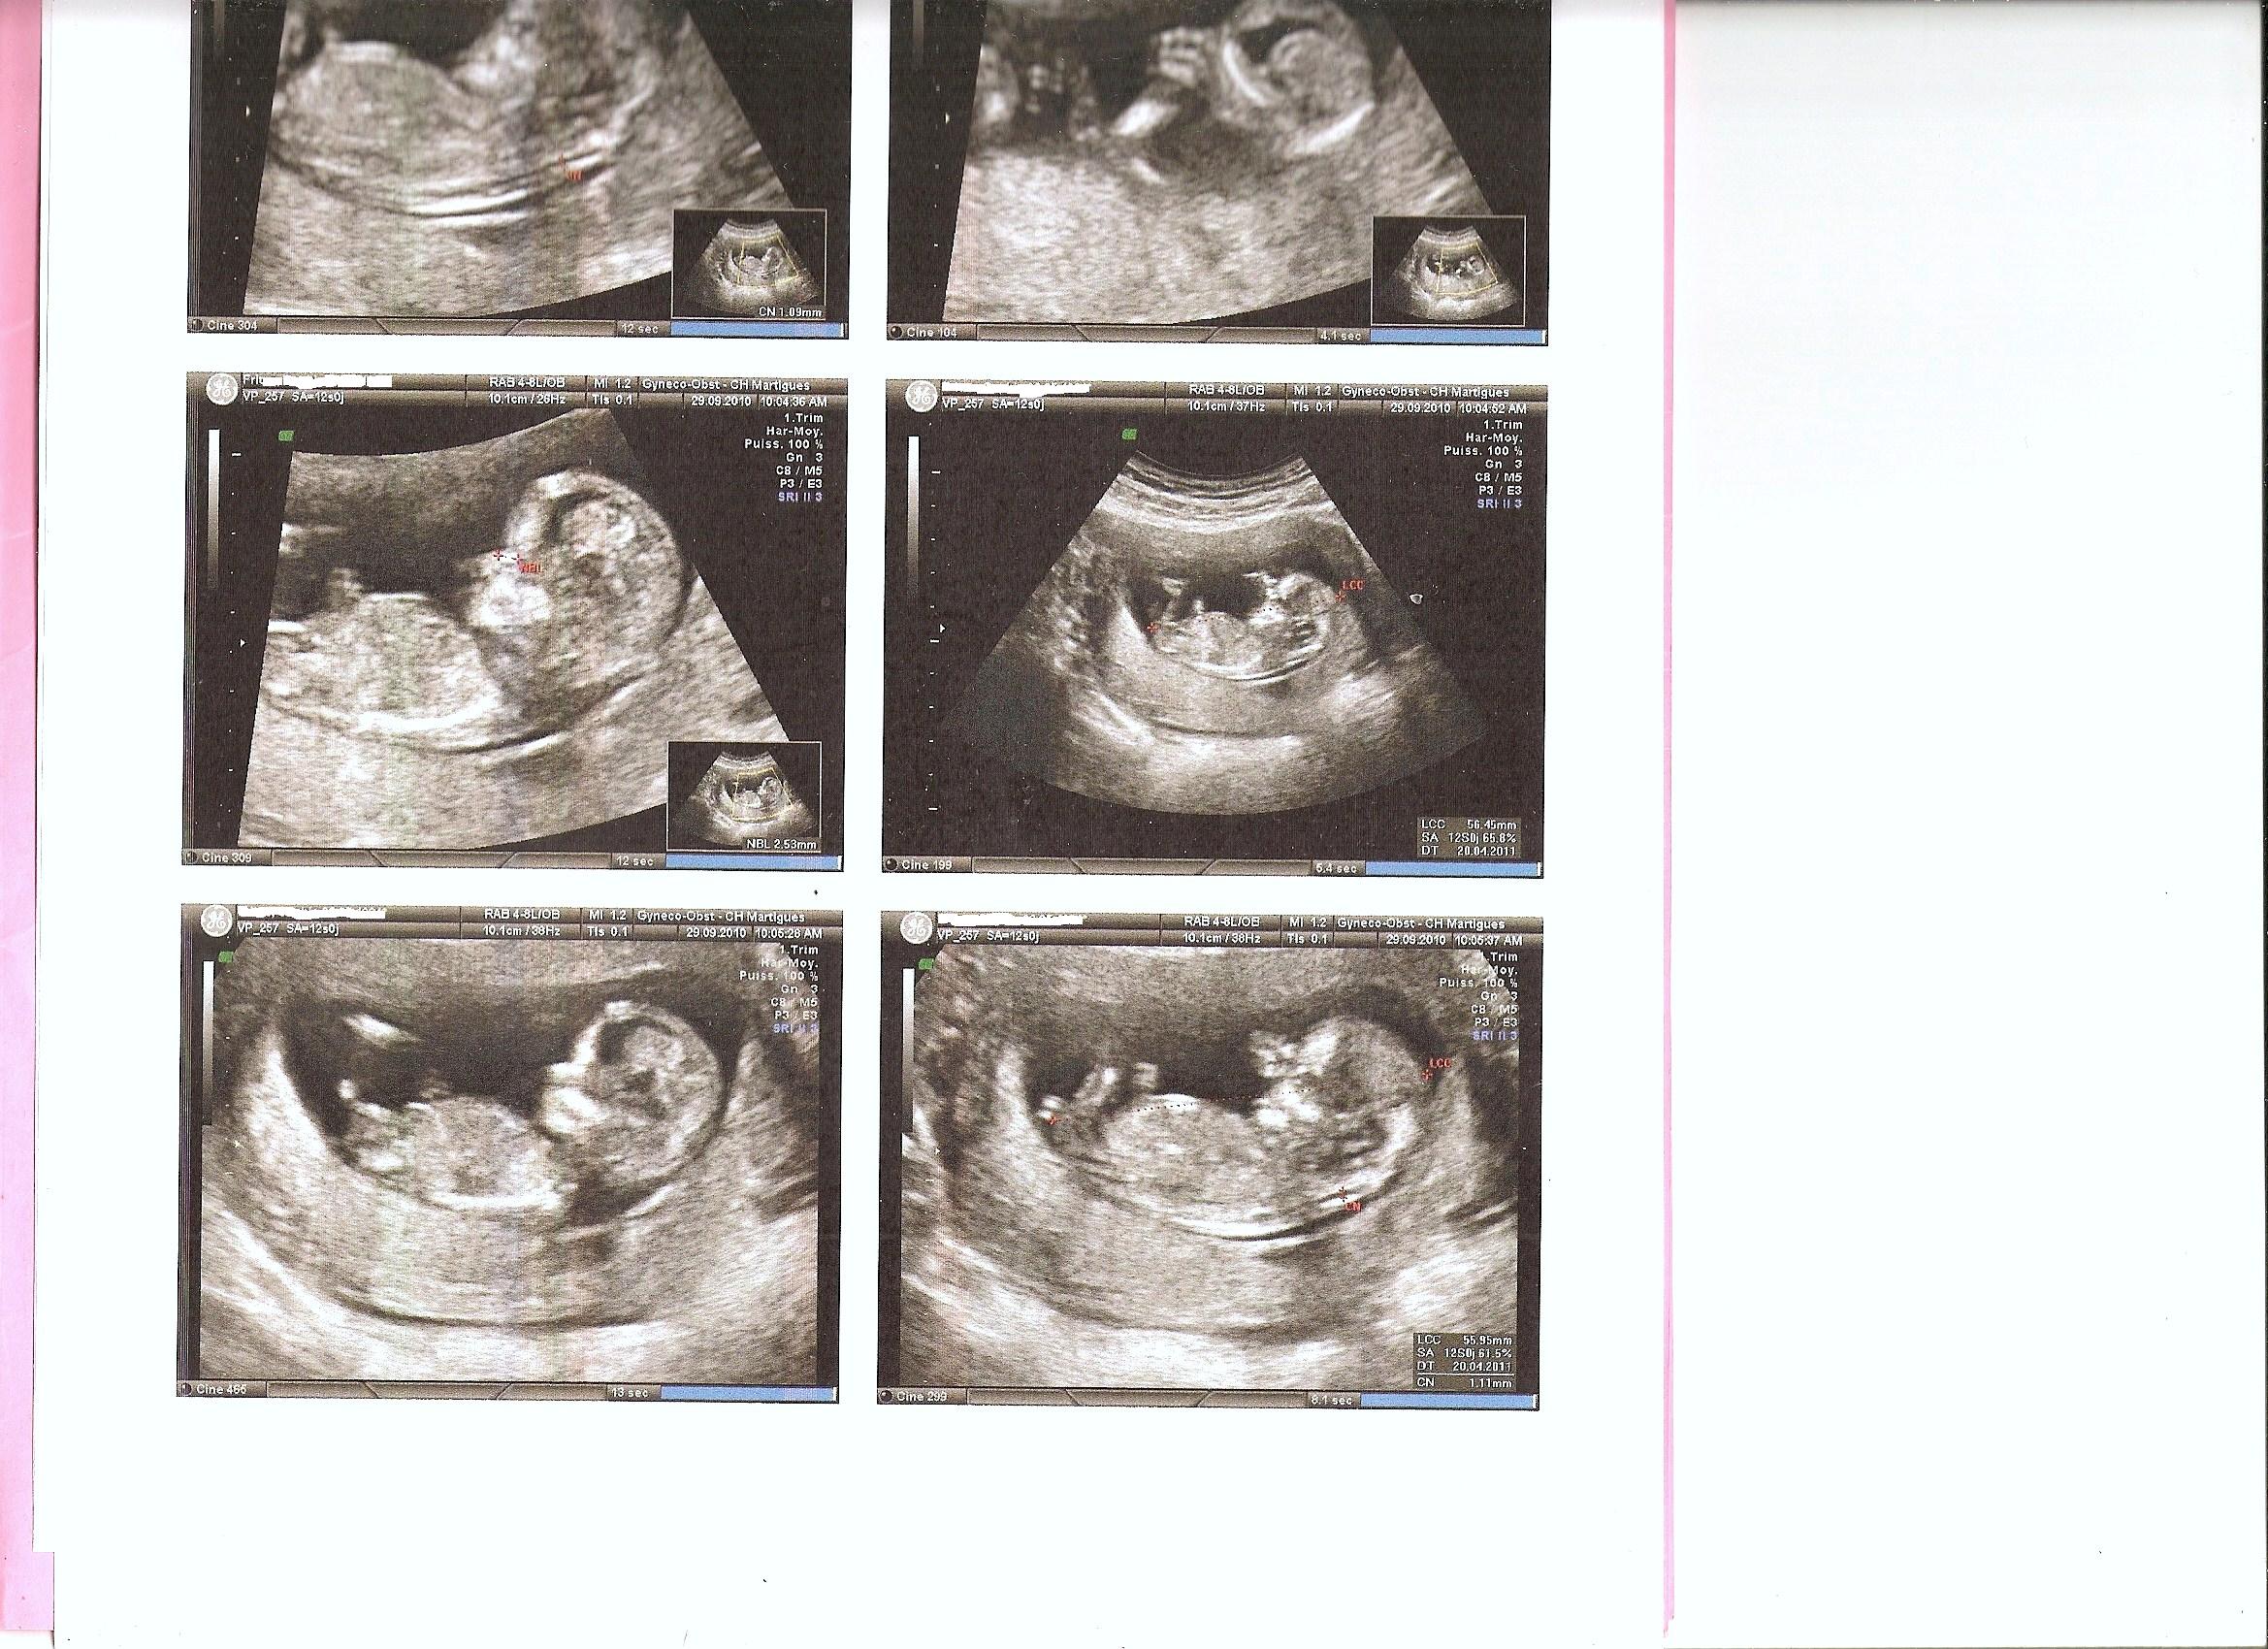

Le fœtus à 31 semaines de grossesse C'est l'heure de la dernière échographie avant la naissance !

Echographie De Grossesse Grossesse 3d Diagnostic Antenatal